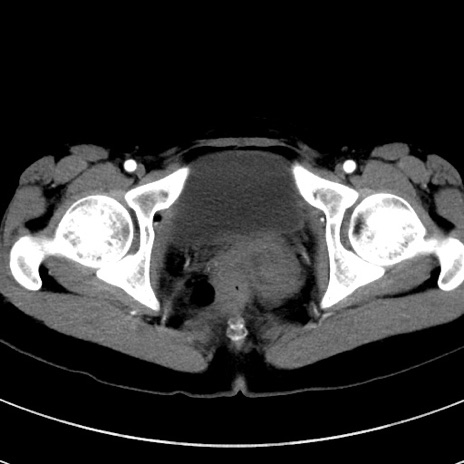

症例17(横断像)

【症例】20歳代女性

【主訴】嘔吐、下腹部痛

【現病歴】昨日夕食後に嘔吐し下腹部痛が出現。本日になっても嘔吐持続し改善しないため来院。

【身体所見】意識清明、BT 37.2℃、BP 108/67mmHg、腹部:平坦、やや硬、下腹部正中から右にかけて圧痛あり、反跳痛軽度あり、tapping pain(+)。

【データ】WBC 13600、CRP 14.94